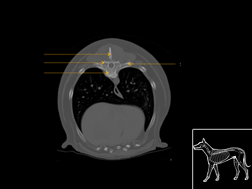

Atlas thorax du chien SCTO

Scanner tissus osseux

>> 23 coupes

Atlas thorax du chien SCTM

Scanner tissu mou

>> 22 coupes